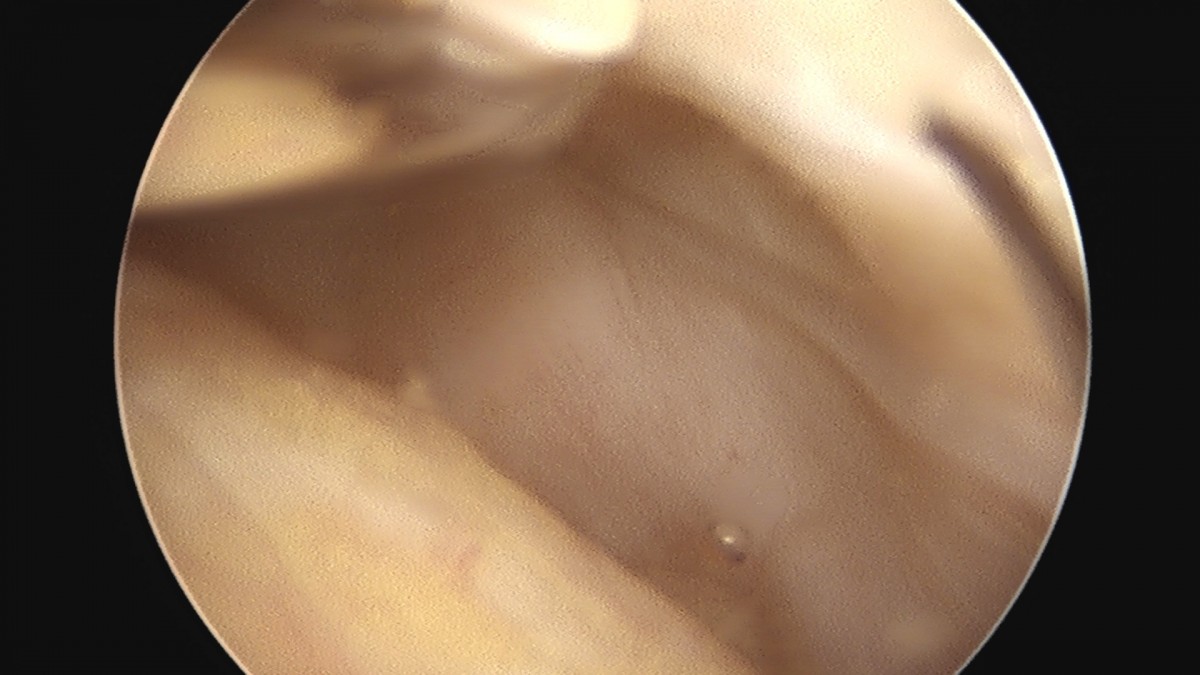

이재상원장님 무릎 반월상 연골판 절제술 홍의O 환자

작성자 최고관리자 댓글 0건 조회 358회 작성일 25-09-16 16:09